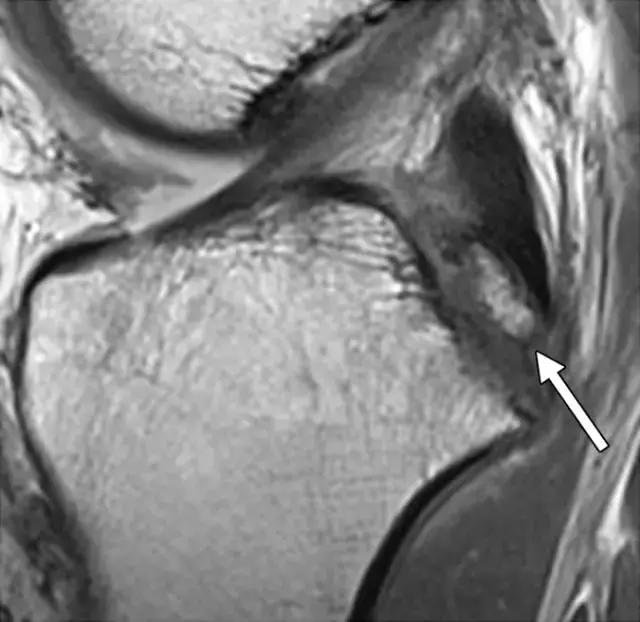

X线照片可能在髁间隙中显示小的骨折片段,或胫前胫骨关节面内的微小透亮区(图7A)。CT可能有助于确定撕裂片段的大小和粉碎程度,如果足够大可以允许螺钉固定片段,并避免ACL的重建。术前MRI也可能有助于评估ACL的外观和识别任何相关的半月板或韧带损伤(图7B)。

图7A -40岁男性前交叉韧带(ACL)撕脱性骨折。膝关节侧位X线照片显示沿胫骨平台前方的微小曲线透亮带(箭头)。

图7B,矢状质子密度加权的MR图像证实ACL嵌入部位的(箭头)撕裂性骨折(箭头)。